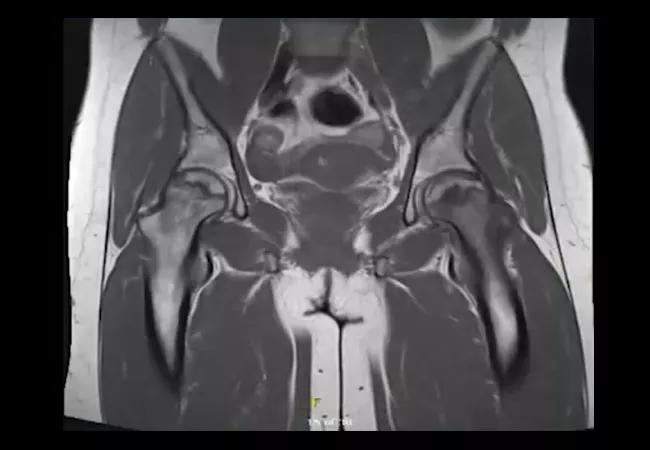

In the emergency department, her hemoglobin A1C was 7.5%, and she was diagnosed with diabetes. A bone densitometry test showed a Z -score of -1.7 in the spine which is less than expected for age. At follow up, she presented with bilateral groin and hip pain, but X-rays did not show obvious avascular necrosis. Bilateral magnetic resonance imaging of the hips showed left-sided acute-on-chronic avascular necrosis and chronic avascular necrosis of the right femoral head with a right-sided joint effusion. She eventually required bilateral hip replacements. Watch as Emily Littlejohn, DO, MPH, staff in the Department of Rheumatologic and Immunologic Diseases, discusses the case.